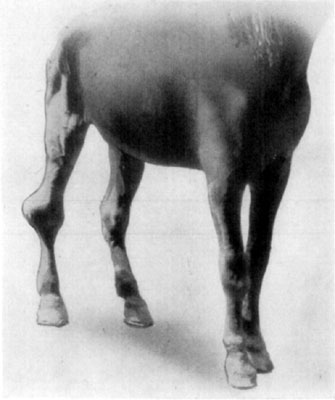

A sequel of chronic lymphangitis is a condition known as elephantiasis. In such cases there occurs a hyperplasia of the skin and subcutaneous tissues, resulting in some instances, in the affected member attaining an enormous size. Sporadic cases of this kind are to be seen occasionally, and are apparently caused by repeated attacks of lymphangitis. The affection is not benefited by treatment, and while a horse's leg may become so heavy and cumbersome as to mechanically impede its gait, as well as to fatigue the subject when made to do service even at a slow pace, elephantiasis causes no constitutional derangement. The hind legs, in elephantiasis, are affected and a unilateral involvement is more often seen than a bilateral one. The legs may be enlarged from the extremity to the body, but ordinarily the affection does not extend higher than the hock or the mid-tibial region.